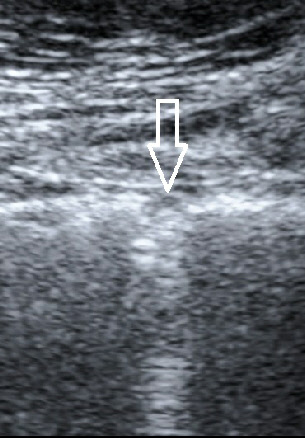

Zoom sur l’alvéologramme hydro-aérique juste en arrière d’un minime alvéologramme hydrique